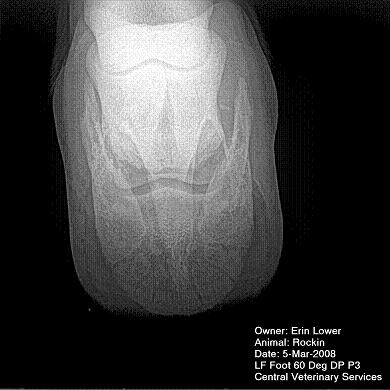

So, Rockin's x-rays were sent to a radiologist and he confirmed "normal" changes in the navicular bones for a horse her age, but slightly more significant ones in the right (sore) foot.

She also has sidebone in both fronts, but apparently that isn't causing any discomfort.

Finally, she has a "small chronic exostosis on the lateral aspect of the proximal phalanx" which, according to the radiologist, shouldn't be causing discomfort but I have read that these can be mild-to-moderately painful... I wouldn't mind another opinion on that.

I will attach as many images as possible from her x-rays (there are many different views). I don't have any pics of the feet as someone deleted them from my camera before I could download them. I'll try to take pics next time she is trimmed. Please, anyone with knowledge of hooves, give any opinions that you might have (especially Dr. O!)

I cannot rule out lesions based on these images but I will take your radiologist's word that he does not see significant lesions. The exostosis on the RF would be above the level of a well conducted PDN which I believed blocked the lameness before?